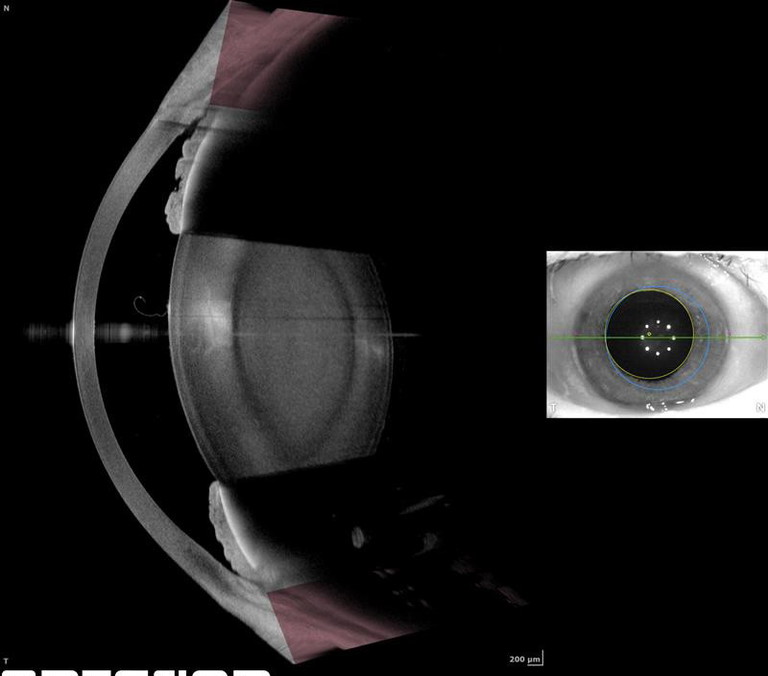

Anterion with Cataract App

Heidelberg’s Anterion with Cataract App combines swept-source optical coherence tomography (OCT) biometry, intraocular lens (IOL) calculation, and anterior segment imaging in a single platform. It streamlines preoperative planning, improves surgical efficiency, and ensures precise, reproducible results. Designed for modern cataract surgery, it delivers reliable data, optimised workflows, and confidence in decision making for every patient.

Contact: Heidelberg (AUS) 03 9639 2125